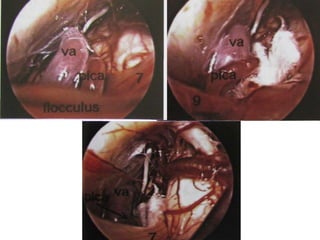

Left side. The 30° angled endoscope

provides an

overview of the inferior part of the

CPA. On the right lies the

acousticofacial nerve bundle, with

the anterior inferior cerebellar

artery; the glossopharyngeal nerve

and the vagus nerve,

as multiple filaments, form three to

five major nerve bundles

and the accessory nerve.

Fig. 74a, b The reference level is the acousticofacial nerve

bundle. The anterior inferior cerebellar artery, lying between

the auditory and facial nerves, is found in 38% of cases.